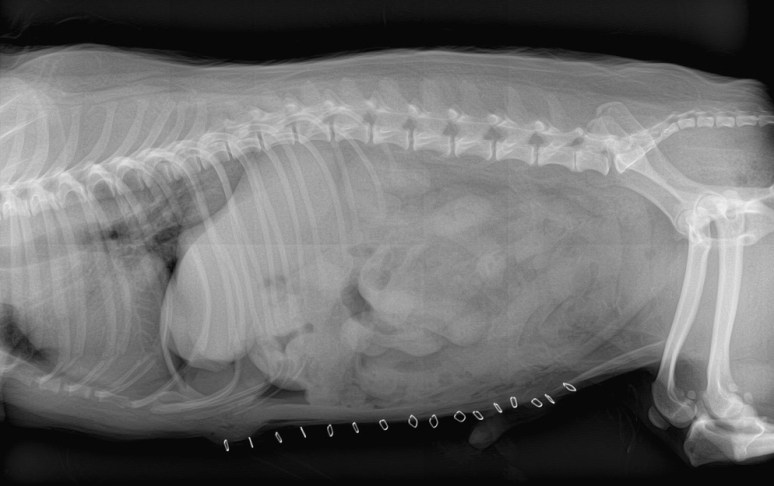

Pas évident ce corps étranger ! Il y a sur la projection latérale une structure très opaque (minérale à métallique) dans le pylore mais cette dernière n’est pas visible sur la projection VD. Pourtant , il y a bien quelque chose dans le pylore sur la VD mais qui semble plus large et d’opacité de tissus mous.

Étant donné que le chien démontrait toujours des signes d’obstruction intestinale, il est allé en laparotomie afin de retirer ce mystérieux corps étranger. On voit sur les radiographies post-op que le corps étranger a bien été retiré.

Et qu’est-ce que c’était ? Un autocollant «puffy» avec un endos métallisé.

Les différences d’opacité relative du corps étranger étaient vraisemblablement liées à son orientation par rapport au faisceau principal, i.e. plus opaque lorsque la tranche était exposée (à cause de la feuille métallisée je présume) et moins opaque de face. Un peu le même principe que les vaisseaux pulmonaires dans le parenchyme.

Et j’imagine que tout le monde a remarqué les jolis calculs urinaires spiculés sur la projection latérale ?